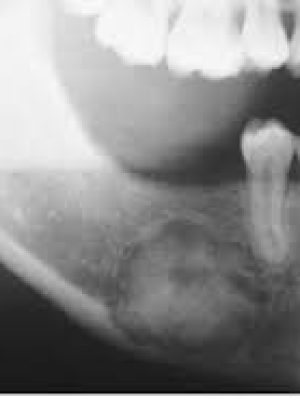

Periodontal diagnosis is complex due to the overlapping nature of clinical signs and symptoms with other dental or systemic diseases. Misdiagnosis can result in ineffective treatment, patient dissatisfaction, and disease progression. This review outlines frequently encountered diagnostic errors in periodontics and offers insights to help general dentists improve diagnostic accuracy in everyday practice.